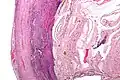

Pathology

Even for clinically certain appendicitis, routine histopathology examination of appendectomy specimens is of value for identifying unsuspected pathologies requiring further postoperative management.[58] Notably, appendix cancer is found incidentally in about 1% of appendectomy specimens.[59]

Pathology diagnosis of appendicitis can be made by detecting a neutrophilic infiltrate of the muscularis propria.

Periappendicitis, inflammation of tissues around the appendix, is often found in conjunction with other abdominal pathology.[60]

Micrograph of appendicitis and periappendicitis. H&E stain.

Micrograph of appendicitis showing neutrophils in the muscularis propria. H&E stain.

Acute suppurative appendicitis with perforation (at right). H&E stain.